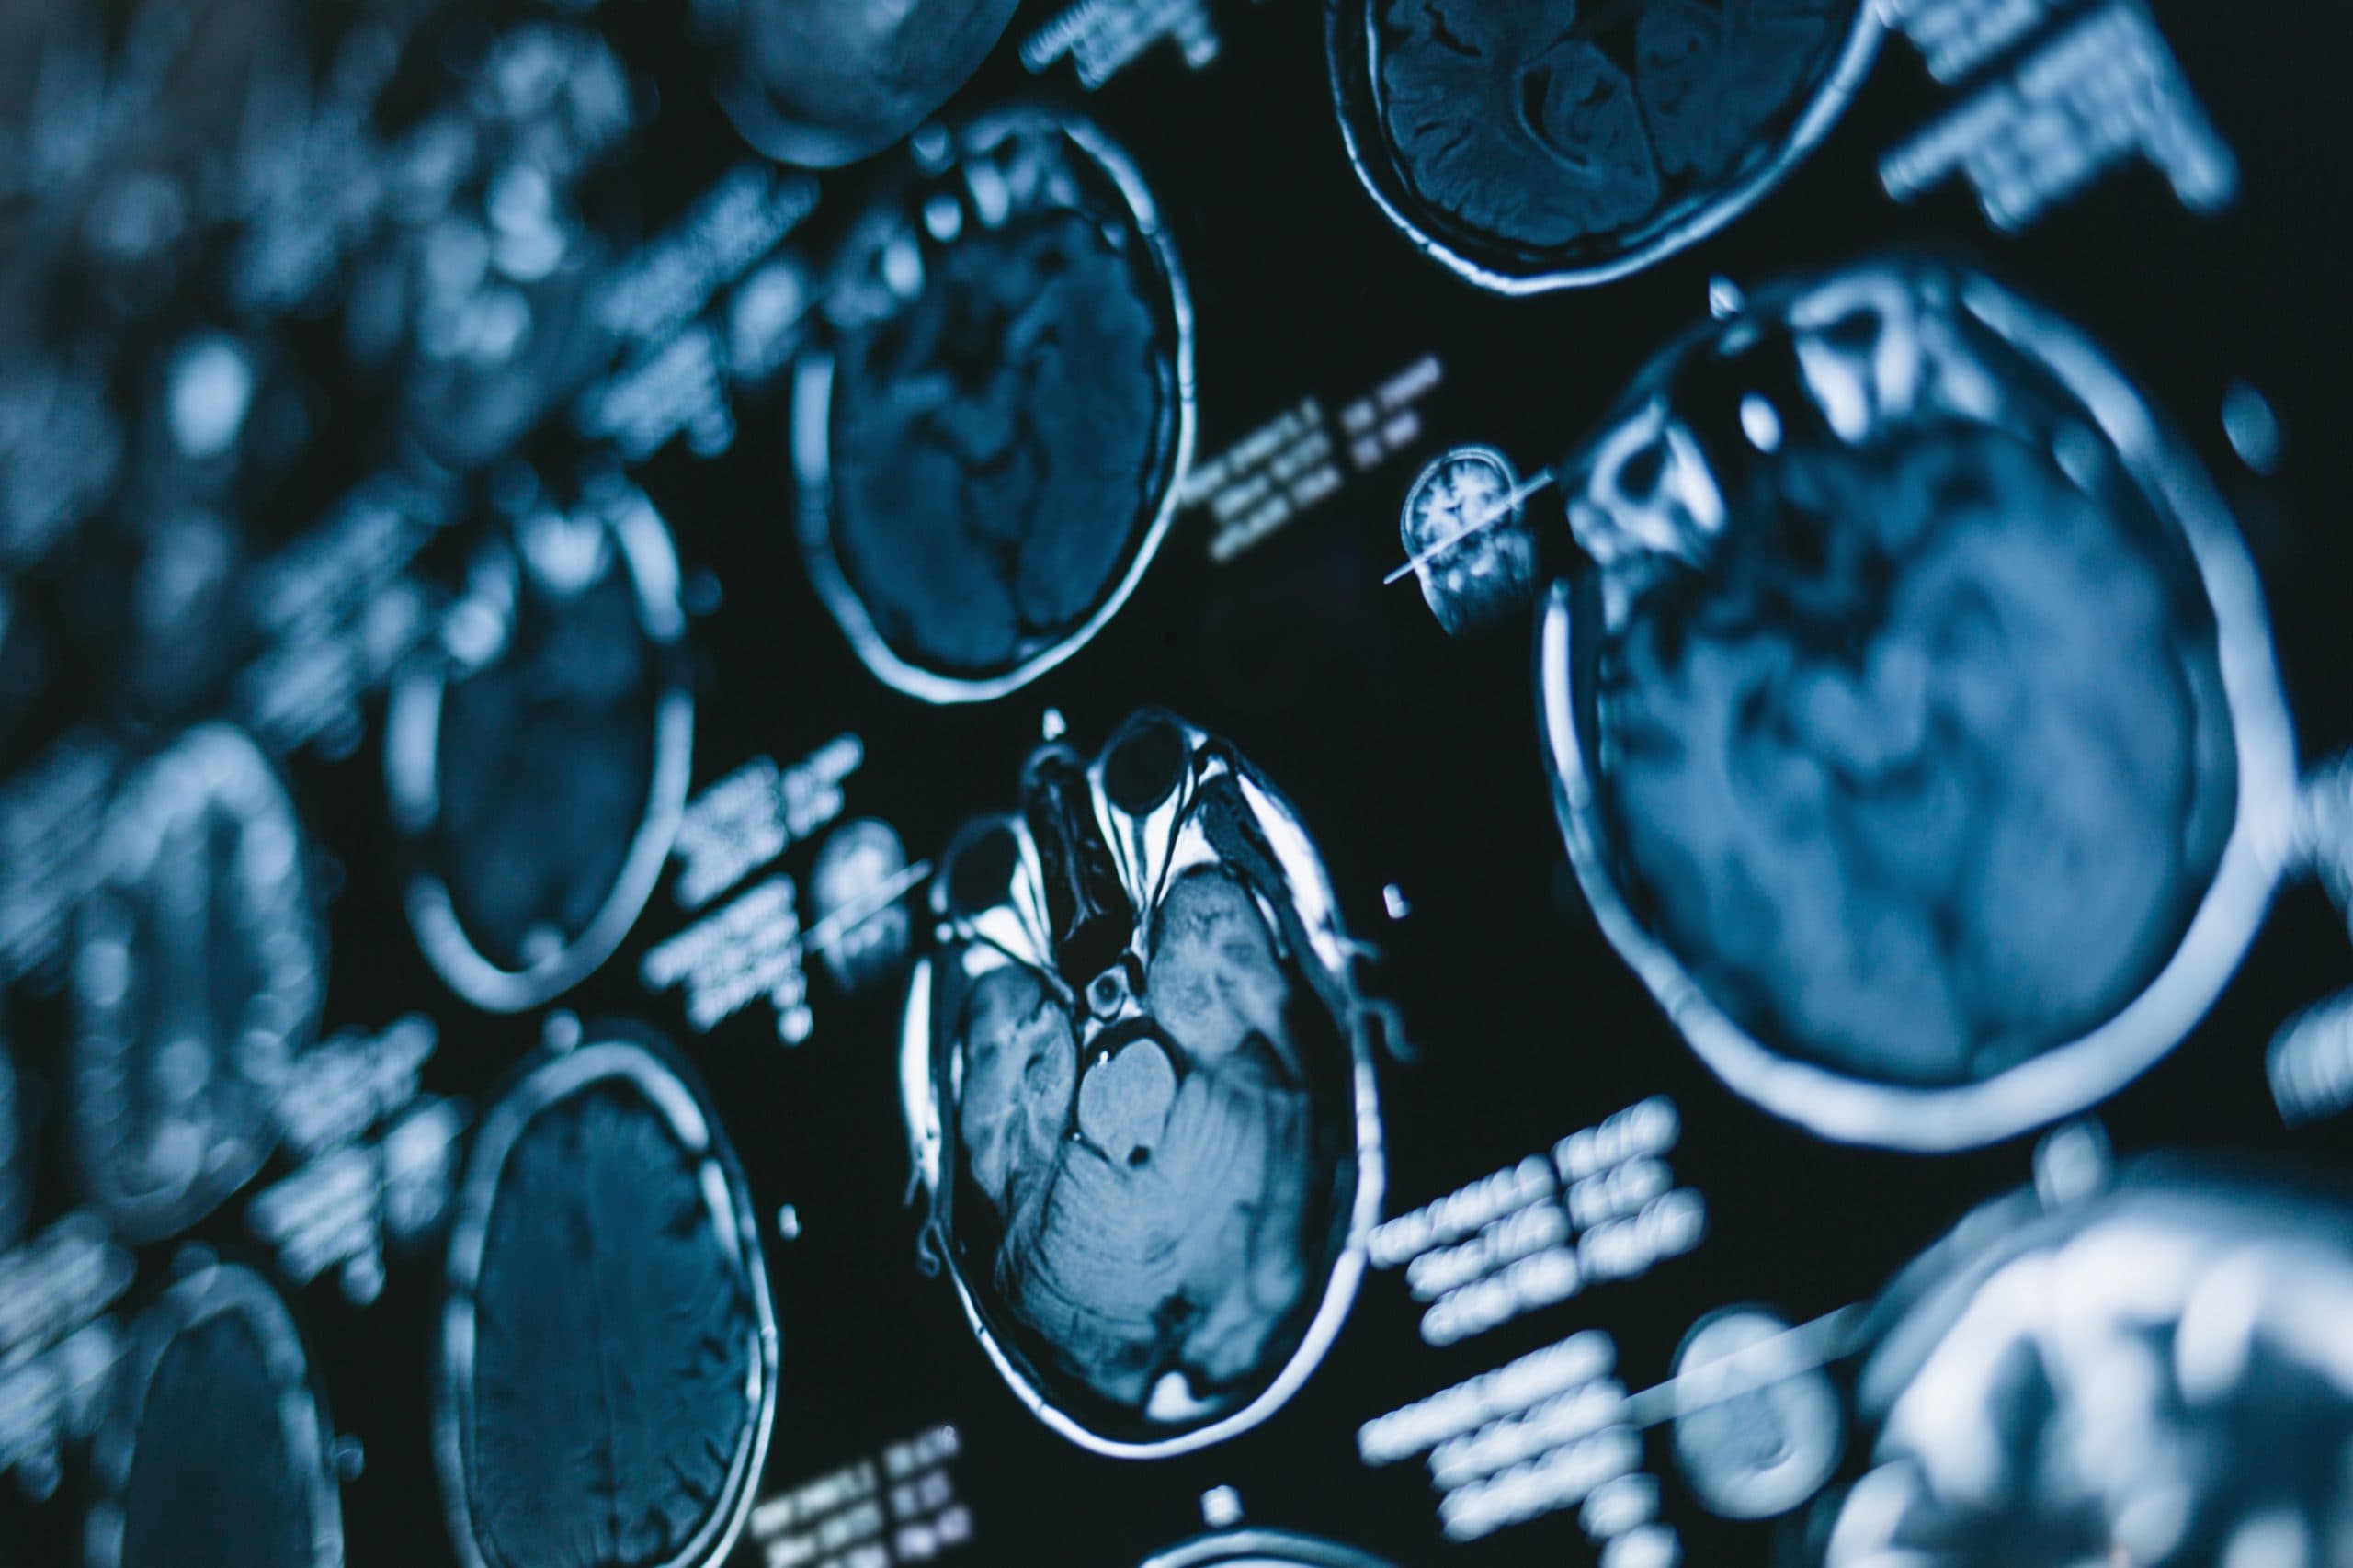

Could AI soon read our minds?

Have you ever wanted to read someone’s mind, or been worried that someone could read yours? Well we might just be one step closer to achieving this according to a new study conducted by researchers from the University of Texas.